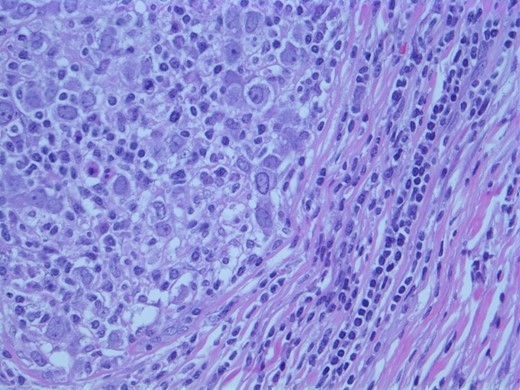

A computed tomographic (CT) scan of her chest with contrast revealed moderate right axillary lymphadenopathy and a lesion in the upper outer quadrant of the right breast measuring 1.3 × 1.2 cm (Fig. 1). A positron emission tomography (PET) scan showed a small intense focus on the right lateral breast consistent with carcinoma, significant right axillary lymphadenopathy and intense fluorodeoxyglucose hypermetabolic activity consistent with metastatic spread. Additionally, enlarged lymph nodes extending along the upper chest wall just inferior to the subclavian vessels and posterior to the pectoralis muscles were seen. A needle biopsy of the mass revealed an extensive involvement of poorly differentiated infiltrating carcinoma (Fig. 2). The tumor showed large nuclei with eosinophilic cytoplasm and prominent nucleoli consistent with apocrine differentiation (Fig. 3). There was a significant inflammatory response to the infiltrating tumor noted. No lymphovascular invasion was identified within the core biopsies. The specimen was estrogen and PR negative as well as HER-2/neu negative.

Photomicrograph: apocrine differentiation and inflammatory response.

The findings were discussed with the patient and she subsequently underwent a modified radical mastectomy. Pathology of the specimens showed poorly differentiated apocrine carcinoma with extensive axillary node metastases (Fig. 4). The invasive carcinoma measured 1.5 × 1.4 × 1.3 cm without invasion into the skin or muscle. The margins were uninvolved.